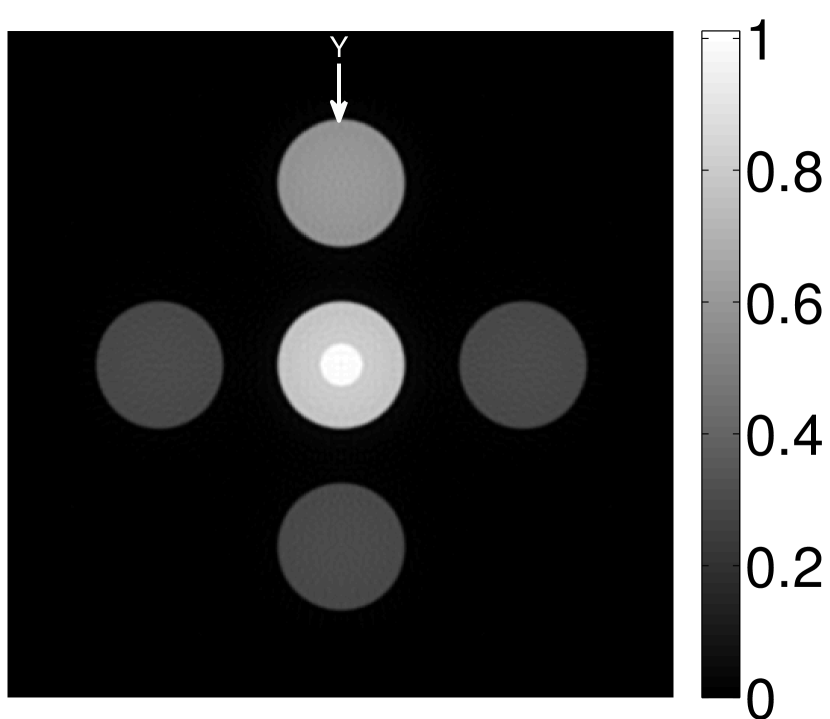

The numerical phantom shown in Figure 1(a) was employed. The phantom had a support area of mm2 and contained six uniform disks that were assigned different values of absorbed optical energy density.

A 2D circular measurement geometry was employed. transducers were evenly distributed on a ring of radius mm that enclosed the phantom. The SOS was assumed to be constant and set at mm/s. Since the simulated data were formed by use of the C-D imaging model in Eqn. (2), no inverse crime was committed. The components of this vector corresponded to equally spaced temporal samples over the interval s. Subsequently, the noiseless voltage vector was obtained by convolving the pressure data with EIR-1 in Figure 1(b).

The reconstruction region ( mm2) was represented by pixels with pixel size mm in each dimension. The initial guess of the EIR employed in the VP algorithm was different than the EIR that was assumed when generating the simulated data. This served to simulate a situation in which an experimentally measured EIR contained errors.

Each element in a real-world transducer array possesses its own EIR. In practice, the differences between the EIRs are sometimes neglected and an EIR corresponding to a single element may be used to represent all elements in the array. In some of the studies below, the EIR employed to initialize the VP algorithm (EIR-2 in Figure 1(b)) and the EIR employed to produce the simulated measurements (EIR-1 in Figure 1(b)) were experimentally measured from two different transducer elements in a circular transducer array (see Sec. VI-B). EIR-1 was measured by temporally integrating the PA signal produced by a point source positioned at the focus of the transducer. EIR-2 was measured by use of the method reported in [RNR2011]. In order to investigate the sensitivity of the VP algorithm to the initialization of the EIR, we employed different EIRs obtained by degrading EIR-1 as described later. When solving the sub-problem in Line-2 of Algorithm 1, was initialized as the zero vector. Algorithm 1 was terminated after 500 iterations, since it was observed that the changes in the reconstructed images with more iterations were negligible. When implemented by use of a single core of an Intel Xeon E5-2640 CPU, each iteration required approximately 7s to complete.

Figure 2(a) shows the image reconstructed by use of the conventional iterative method that utilized a system matrix based on EIR-2. Different values of the regularization parameter from the interval were considered. The reconstructed image with the value of that minimized the RMSE was chosen to represent the best performance of the conventional iterative method. Figure 2(a) and the profile in Figure 2(c) demonstrate that the use of an inaccurate EIR can result in strong artifacts and distortions in images reconstructed by use of the conventional methods.

When the VP algorithm was applied, different values of the regularization parameter from the interval and from the interval were considered. The image that minimized the RMSE was chosen and displayed in Figure 2(b). As revealed by this image and the profiles in 2(c), the VP algorithm yielded an image with fewer artifacts and distortions, and image fidelity was improved as reflected by the reduced RMSE.

V-A3 Effect of data incompleteness

Incomplete, or sparsely sampled, data sets are sometimes acquired in practice. To study the effect of data incompleteness on the VP algorithm, we reconstructed images from data corresponding to half of the equally spaced transducers (). Because the data were noiseless, no explicit regularization was employed () in the conventional reconstruction algorithm. However, the explicit regularization was still employed in the VP algorithm because of the ill-posed nature of the joint reconstruction problem. The results are shown in Figure 5. As expected, use of the incomplete data set resulted in less accurate reconstructed images for both the conventional iterative reconstruction method and the VP algorithm. However, this effect was more pronounced for the VP algorithm. Note that for the VP algorithm, larger values of the regularization parameters were applied when the incomplete data set was employed than when the complete data set was employed (Figure 5(h) and 5(g)).